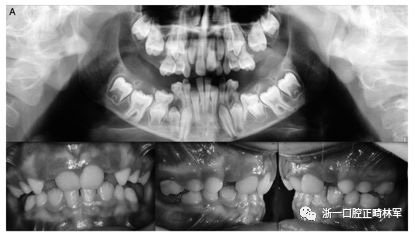

圖1.(A,B)兩兄弟的口內(nèi)照片。全景:外顯子5的下游變體(CTCF結(jié)合位點(diǎn))rs113566258 SNPc.313±32A>G; 在外顯子16中的變體(位置3:46903467)c.1593-95 Del C,p.531 / 532; 外顯子10中的同義變體(位置3:46899419)c.1152 G>A.

兄弟姐妹被診斷為I型PFE并顯示雙邊呈現(xiàn)。該變體(PTH1R基因的外顯子5的下游c.313×32 A.G)發(fā)生在與轉(zhuǎn)錄因子相互作用的調(diào)節(jié)區(qū)中。除了這種突變之外,這些兄弟還受到第二個(gè)突變的影響,這些突變對(duì)每一個(gè)都是獨(dú)特的:一個(gè)兄弟姐妹(II:1)也存在在外顯子16的基因氨基末端發(fā)生的移碼缺失,c.1593DelC ,第(Pro532Leufs *)(圖1A,B)。在另一個(gè)同胞(II:3)中,鑒定出在蛋白質(zhì)氨基酸序列水平不引起變異的外顯子,c.1152GA(rs200475872;圖1A,B)中的同義變體,但涉及改變含氮堿。基于計(jì)算機(jī)分析,這種改變可能會(huì)影響mRNA的折疊并影響其半衰期和蛋白質(zhì)生產(chǎn)。在這個(gè)患者樣本中,在一個(gè)孤立的病例中發(fā)現(xiàn)了同樣的同義變體c.1152G.A,由于PFE而具有嚴(yán)重的開合(圖2)。

圖2.口內(nèi)照片。全景:外顯子10中的同義變體(位置3:46899419)c.1152 G>A.